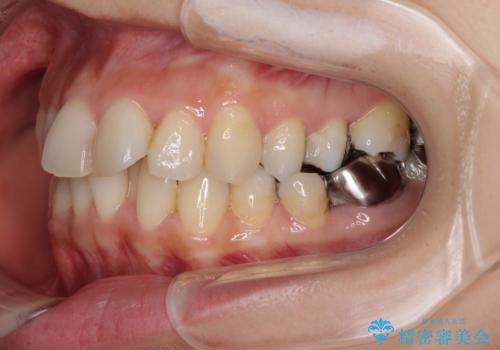

- 上下のデコボコと奥歯の咬みにくさを気にして来院された患者様です。

上顎骨の幅が下顎骨よりも小さいので、拡大装置により骨幅を広げて上下関係を改善し、その後インビザラインにて歯並びを整えることとしました。

上下の骨幅を改善したことで、スムーズに歯列矯正を行うことができました。

矯正治療中に近医で銀歯を外す治療を開始したため、治療後に奥歯の咬み合わせが不十分ですが(こちらは近医での治療により改善するとのこと)、歯列と咬み合わせが改善され、患者様には大変満足していただきました。